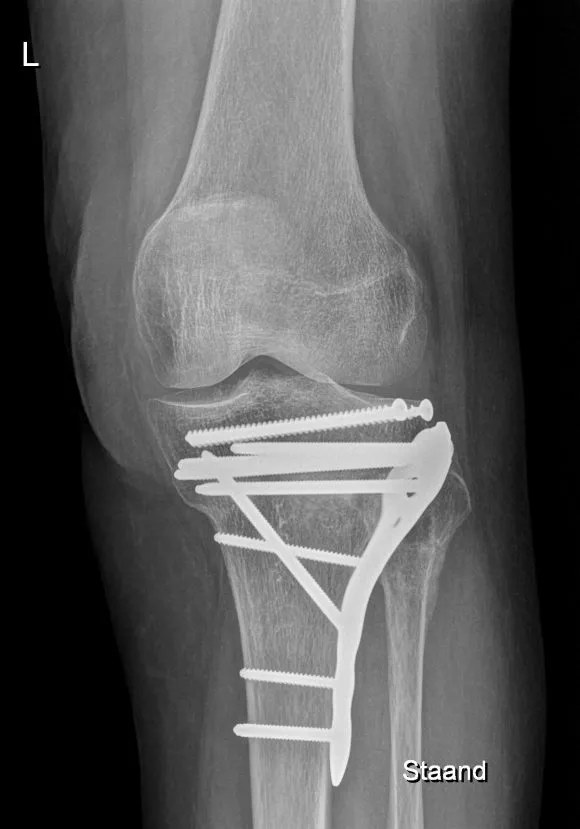

- Open repositie en interne fixatie (ORIF): De chirurg maakt een incisie aan de gebroken zijde (binnen- en/of buitenkant, soms ook aan de achterkant) van de knie. De indeuking van het plateau wordt voorzichtig omhoog gedrukt. Vaak wordt het onderliggende gat opgevuld met donorbot om het op hoogte te houden. Vervolgens worden een plaat en schroeven aangebracht om de fragmenten vast te zetten. Bij een laterale tibiaplateaufractuur aan de buitenzijde van het tibiaplateau gebruikt men vaak een enkele laterale L-vormige plaat met schroeven. Bij bicondylaire fracturen kunnen zowel een laterale als een mediale of posterieure (buiten-, binnen- of achterkant) plaat nodig zijn. De schroeven fixeren de losse stukjes gewrichtsvlak weer aan elkaar en aan de rest van het bot.

- Na de operatie wordt de stabiliteit gecontroleerd en een controle röntgenfoto gemaakt. Meestal laat men binnen 1-2 dagen de mobilisatie starten. De patiënt mag vaak 6 tot 12 weken niet op het been steunen of slechts gedeeltelijk (10-15 kg) belasten, zodat het herstel niet in gevaar komt. Tegelijk wordt veel aandacht besteed aan vroegtijdige beweging van het kniegewricht om stijfheid te voorkomen. Soms wordt een scharnierbrace ingesteld die beperkte buiging toelaat (bijvoorbeeld eerste 2 weken 0-30°, daarna gradueel opbouwen). Met hulp van een kinesist gaat de knie passief en actief beetje bij beetje meer plooien. Doel is vaak om binnen enkele weken 90° buiging te behalen, al lukt dat niet altijd door pijn en zwelling.

Een tibiaplateaufractuur is een ernstige kniebreuk waarbij het gewrichtsoppervlak van het scheenbeen is gebroken en vaak ingedrukt. Het treedt op door flinke trauma’s (val, ongeval) of bij osteoporose na een val. Symptomen zijn onder meer kniezwelling, hevige pijn en het onvermogen het been te belasten. De diagnose wordt bevestigd met röntgenopnamen en meestal een CT-scan vanwege de complexiteit. De behandeling bestaat vaak uit een operatie om het gewricht zo goed mogelijk te herstellen en met platen en schroeven vast te zetten. Niet-verplaatste breuken kunnen eventueel zonder operatie genezen met gips/brace en rust. Het herstel vergt een lange revalidatie met initieel niet steunen op het been en intensieve kiné om de knie weer mobiel te krijgen. Hoewel veel patiënten terugkeren naar een acceptabele kniefunctie (wandelen, fietsen, lichte sport), is volledige herstel zoals voor het ongeval niet altijd haalbaar; enige beperkingen in beweeglijkheid of belastbaarheid en een risico op knieslijtage zijn aanwezig. Met de juiste behandeling en begeleiding, is de knie meestal weer stabiel en bruikbaar voor het dagelijks leven, en kunnen ernstige gevolgen voorkomen worden.